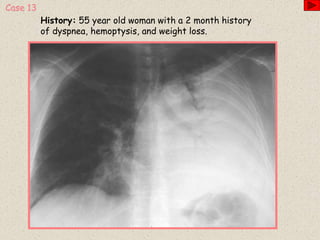

History: 55 year old woman with a 2 month history

of dyspnea, hemoptysis, and weight loss.

Case 13

Diagnosis

Bronchioloalveolar carcinoma of the lung

 A distinct form of adenocarcinoma of the lung

 Characterized by growth along the walls of preexisting normal lung air spaces

without disturbance or destruction of lung parenchyma

 Radiographically, can appear as a solitary pulmonary nodule, diffuse nodules, or as

airspace consolidation

 One of a few lung tumors that demonstrates the air bronchogram sign